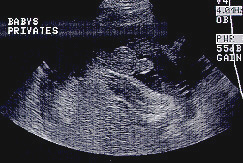

الولد

ولد في الأسبوع ال 15

ولد في الاسبوع ال16

الأسبوع ال17

الأسبوع ال18